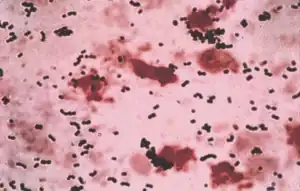

| Streptococcus agalactiae- Gram stain | |

As mentioned, S. agalactiae is a Gram-positive coccus with a tendency to form chains, beta-haemolytic, catalase-negative, and facultative anaerobe. GBS grows readily on blood agar plates as microbial colonies surrounded by a narrow zone of β-haemolysis. GBS is characterized by the presence in the cell wall of the group B antigen of the Lancefield classification (Lancefield grouping) that can be detected directly in intact bacteria using latex agglutination tests.[19][20][21]